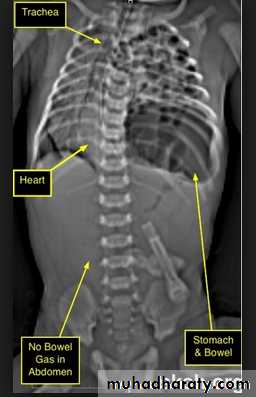

Massive pleural effusion with mediastinal shift to the left.

(A) Chest radiograph

(B) CT coronal reconstruction. A massive effusion displaces the mediastinum to the left. CT shows the important pleural effusion together with the enhanced atelectatic left lung.

Note also the depression of the right hemidiaphragm (arrows).